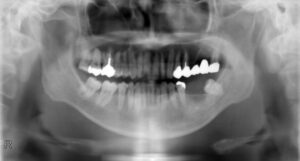

下顎大臼歯2本欠損症例

BEFORE AFTER 67歳男性/下2本欠損/インプラント埋込手術 【治療内容】 他院にて左下の奥歯を抜歯後5年間放…